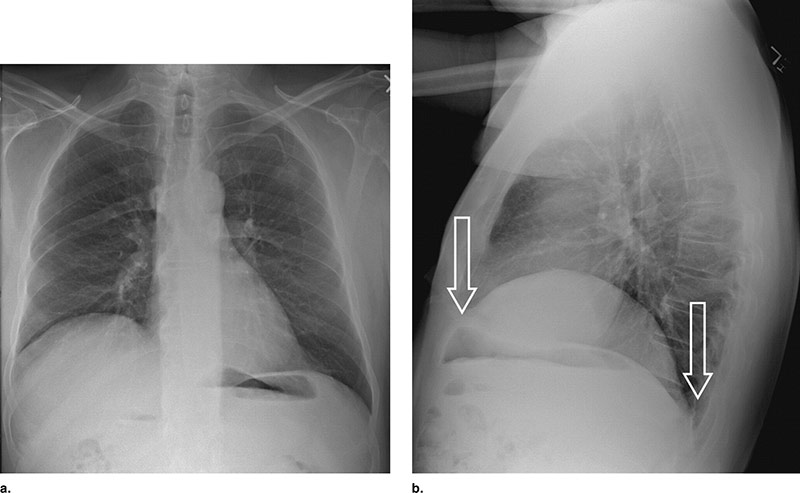

A Eventração Diafragmática (ED) é caracterizada pela elevação total ou parcial da cúpula do diafragma. Ela está relacionada com a perda de mobilidade e faz com que o músculo pare de auxiliar na ventilação pulmonar.

Nessa anormalidade a sua musculatura adquire um aspecto flácido e facilita que os órgãos do abdômen se movam para a cavidade do tórax.

O diagnóstico dessa doença é feito através de uma ultrassonografia realizada em tempo real ou com Ressonância Nuclear Magnética.